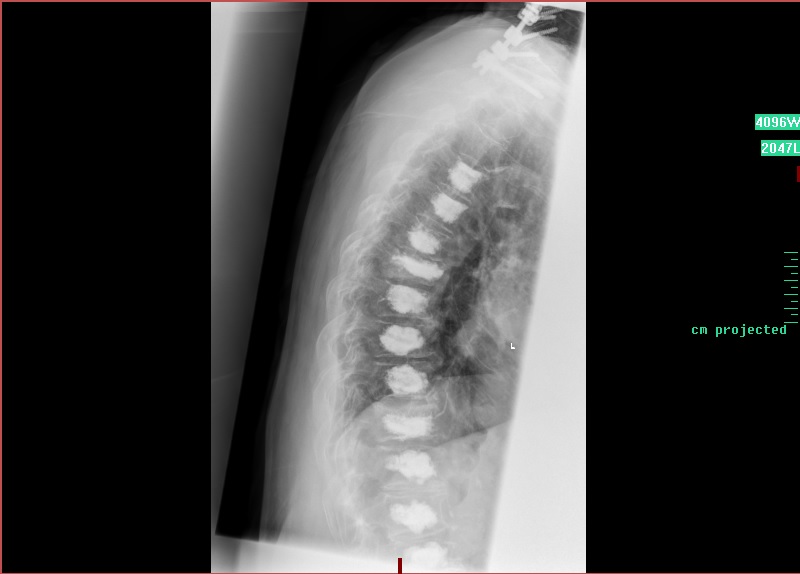

„Das Gute bei der Kyphoplastie ist, dass die Wirbelkörper stabilisiert werden und die Wirbelsäule nicht versteift“, sagt Chefarzt Dr. Richard Delebinski. Die Beweglichkeit bleibt also erhalten. Das Verfahren ist minimal-invasiv möglich, also über kleinste Zugänge – in diesem Fall zur Wirbelsäule. Dort wird über einen Zugang der Knochenzement so gleichmäßig verteilt, dass dadurch der zusammengebrochene Wirbel wieder aufgebaut wird. Gleich am ersten Tag nach der OP ist der Patient wieder mobil.

Damit das nicht passiert, geht Delebinski nun einen Schritt weiter. „Es hätte keinen Zweck gehabt, wieder nur die gebrochenen Wirbel zu operieren“, sagt Delebinski. Stattdessen stabilisiert er nun die komplette Wirbelsäule mit Knochenzement. „Da es sich um eine weit fortgeschrittene Osteoporose-Erkrankung handelt, war die Wahrscheinlichkeit hoch, dass auch die restlichen Wirbel nach und nach brechen.“